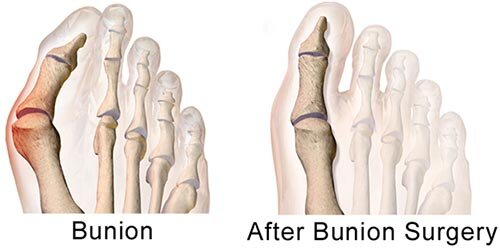

A hammer toes is a toe that curls or is buckled. This condition can be very painful and make fitting into shoes difficult. This deformity can cause skin lesions where infection introduction can occur mainly seen in diabetes or those with poor circulation. See a Manhattan hammer toe surgeon or foot doctor in New York sooner rather than later to treat this uncomfortable condition.

People ask NYC podiatrist every day to explain what caused their toe to become bent like this. This deformity occurs when the muscles that stabilize your toes lose the delicate balance among them and start to overpower each other. This causes your toe to bend or become stuck in a curled position. This can become painful because the contracted toes bump against the top of your shoe. The ball of the foot can also become painful since the toes are not carrying any weight as they contract off the ground. It’s possible for less invasive methods to help, but if your case is serious, your NYC podiatrist may recommend hammer toe surgery.